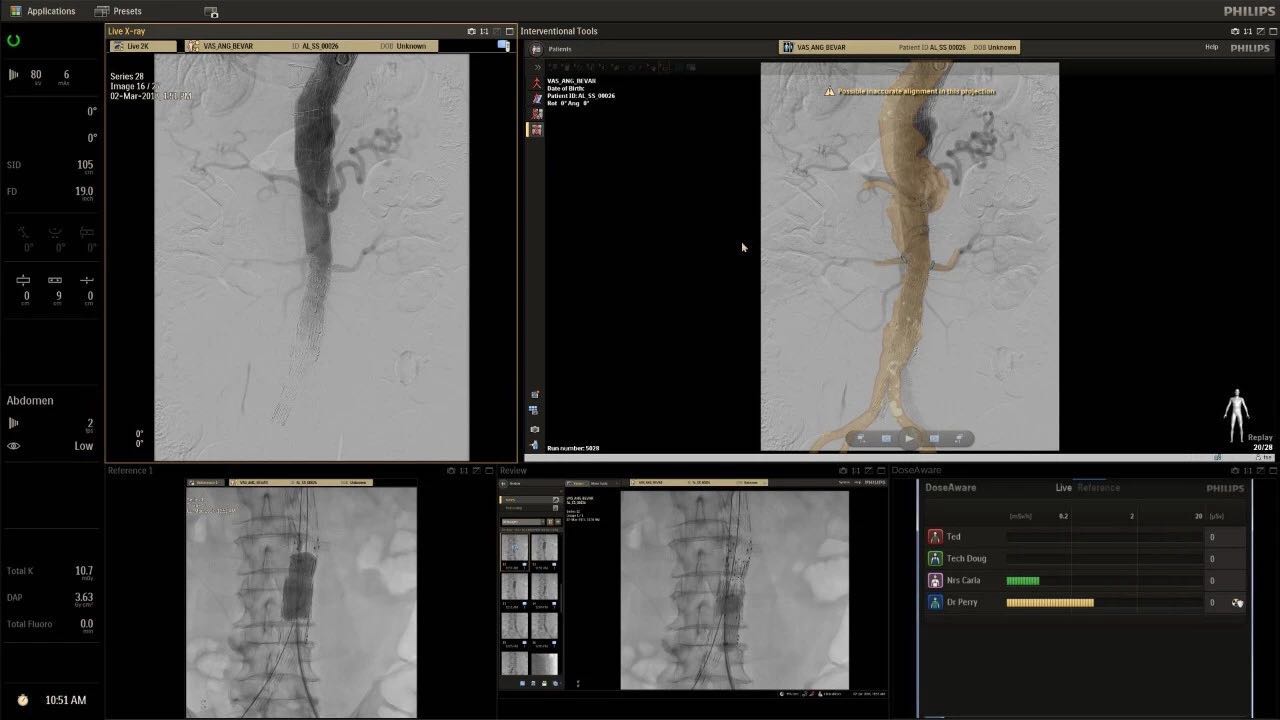

帶有FlexArm的Azurion 7 C20 包含一系列創(chuàng)新技術(shù),使臨床醫(yī)生可以更輕松地在整個(gè)患者身上進(jìn)行二維和三維成像。當(dāng)臨床醫(yī)生移動(dòng)系統(tǒng)時(shí),圖像光束自動(dòng)保持與患者的對(duì)準(zhǔn),允許更一致的可視化并使他們能夠?qū)⒆⒁饬性谥委熒稀?/span>

飛利浦表示,采用FlexArm設(shè)計(jì)的Azurion 7 C20可提供卓越的靈活性和直觀的控制。該系統(tǒng)由智能運(yùn)動(dòng)引擎驅(qū)動(dòng),可在八個(gè)不同的軸上移動(dòng),所有這些軸均由其單個(gè)“Axsys”控制器控制。臨床醫(yī)生的模擬測(cè)試表明,該系統(tǒng)有可能顯著減少患者,工作人員和設(shè)備的重新定位,從而改善微創(chuàng)手術(shù)的可及性,包括通過(guò)患者手腕進(jìn)入身體的手術(shù)(橈動(dòng)脈入路),并降低患者的風(fēng)險(xiǎn)。無(wú)意中拔出電線和管子,以及節(jié)省大量時(shí)間。該系統(tǒng)非常適合混合手術(shù)室(OR),可滿足一個(gè)房間內(nèi)的多種專業(yè)需求,例如手術(shù)和血管內(nèi)手術(shù)的組合。

(FlexArm在不少于8軸的情況下旋轉(zhuǎn),從而創(chuàng)建幾乎無(wú)限的靈活性來(lái)執(zhí)行成像,從頭部到腳部在左側(cè)和右側(cè)進(jìn)行2D和3D可視化。圖像光束保持與患者對(duì)齊,允許在旋轉(zhuǎn)或角度期間更好地可視化解剖結(jié)構(gòu)。使用Axsys運(yùn)動(dòng)控制系統(tǒng)輕松操作支架。)